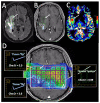

In the follow-up treatment of high-grade gliomas (HGGs), differentiating true tumor progression from treatment-related effects, such as pseudoprogression and radiation necrosis, presents an ongoing clinical challenge. Conventional MRI with and without intravenous contrast serves as the clinical benchmark for the posttreatment surveillance imaging of HGG. However, many advanced imaging techniques have shown promise in helping better delineate the findings in indeterminate scenarios, as posttreatment effects can often mimic true tumor progression on conventional imaging. These challenges are further confounded by the histologic admixture that can commonly occur between tumor growth and treatment-related effects within the posttreatment bed. This review discusses the current practices in the surveillance imaging of HGG and the role of advanced imaging techniques, including perfusion MRI and metabolic MRI.